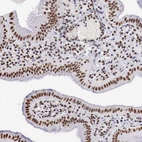

Immunohistochemical staining of human gall bladder shows distinct nuclear positivity in glandular cells.